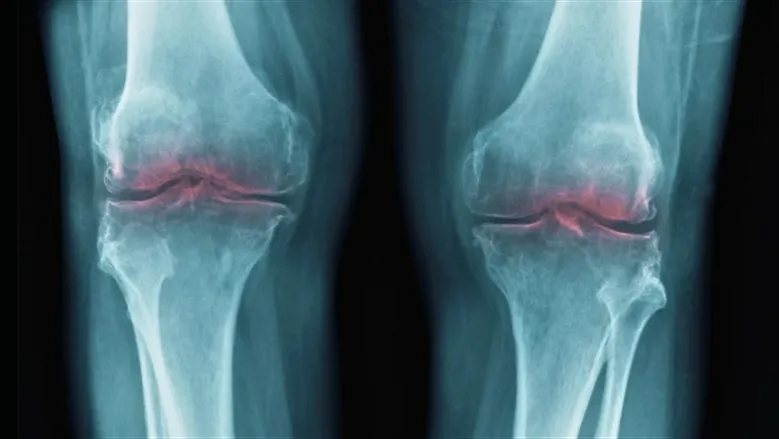

دراسة جديدة تكشف عن بروتين يمكن أن يكون مفتاحًا لعلاج فقدان الغضروف وآلام المفاصل. البروتين المعروف باسم 15-PGDH أصبح مرتبطًا بفقدان الغضروف مع تقدم العمر — وهو اكتشاف قد يغير قواعد اللعبة.

مع تقدم العمر، يزداد مستوى البروتين 15-PGDH، مما يساهم في تدهور الغضروف. هذا الاكتشاف يمثل خطوة نحو فهم أعمق لآلية فقدان الغضروف وكيفية معالجته.